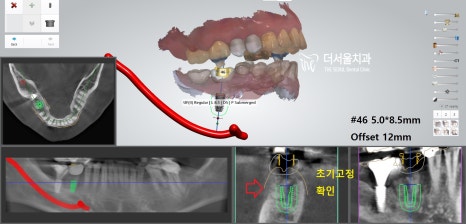

『# 14 # 15 # 46 implant

디지털 방식의 분석을 이용하여

식립 방향 및 각도를 결정하고

최종적으로 심어질 위치까지 선정했습니다.

이후 계산된 곳에 튼튼한 픽스처를 심어드렸죠.

# 47은 심어져있던 픽스쳐 위에

크라운을 올려드려야 되는 과정이라

어려움이 있었는데요.

# 47 기존 크라운 제거

방사선 엑스레이 촬영으로

제품명과 사이즈를 판독한 뒤

관련 부품을 수급하여

# 46 크라운을 올릴 때 같이 해드렸습니다.